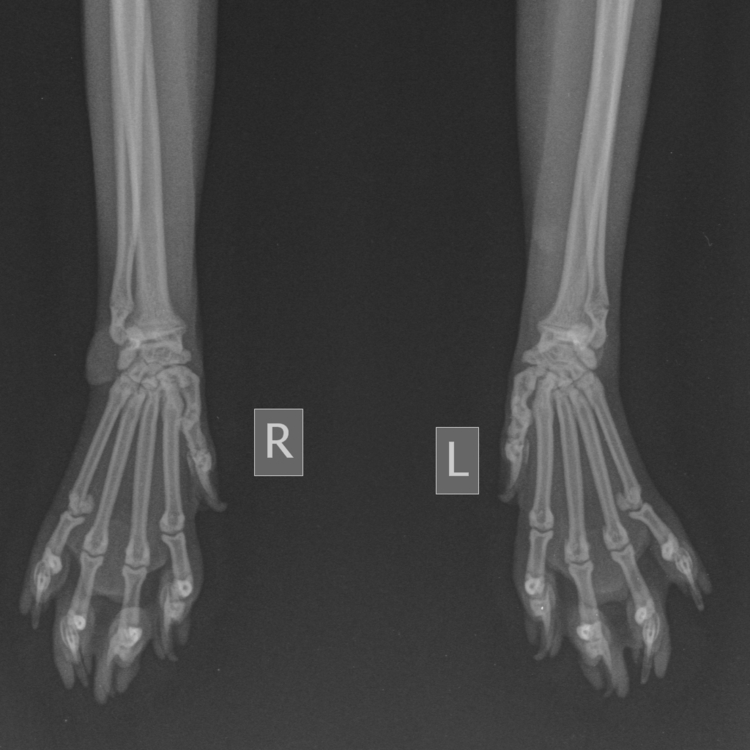

No i skończyło się rumakowanie, łapa pęknięta ☹️

Nie mamy pojęcia, zauważyliśmy, że lekko utyka, ale nie cały czas i w ogóle ciężko było to zaobserwować.  Pierwszy weterynarz stwierdził, że ma mało jakiejś mazi miedzy kośćmi nadgarstka, dał jakiś zastrzyk oraz suplementację kolagenem i kazał przyjść do kontroli na drugi dzień. W drugim dniu na kontroli inny weterynarz stwierdził, że coś jest nie tak w łokciu i zlecił RTG. Finalnie poszliśmy na RTG do trzeciego i wyszło pęknięcie w nadgarstku.

To złamanie nie w nadgarstku ale wyżej. Złamana kość łokciowa w 1/4 dalszej, przerwana jedna korówka, takie trochę zlamanie tzw. zielonej gałązki.

No tak tak, nad nadgarstkiem. Masz z tym jakieś doświadczenie? Weterynarz stwierdziła, że powinno się samo zrosnąć, mamy zrobić prześwietlenie za 3 tygodnie. Myślisz, że iść jeszcze gdzie indziej?